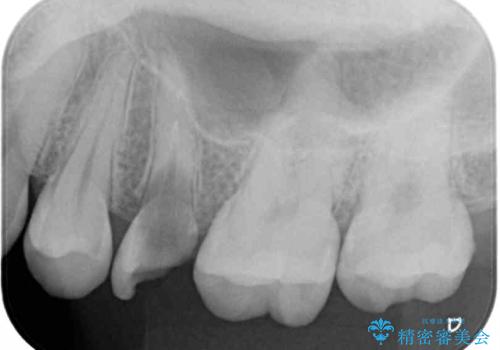

- 根管治療が必要な虫歯を放置した結果、抜歯が必要と診断されたとのことで来院された患者様です。

口腔内の状態やレントゲン写真から判断し、長期的なことを考えると抜歯が無難と思われましたが、それを承知の上で保存するための処置を行うこととしました。

まずは虫歯を除去した上で根管治療を行い、部分矯正により骨内深い位置にまで及んだ健全な部分を引っ張り出すこととしました。